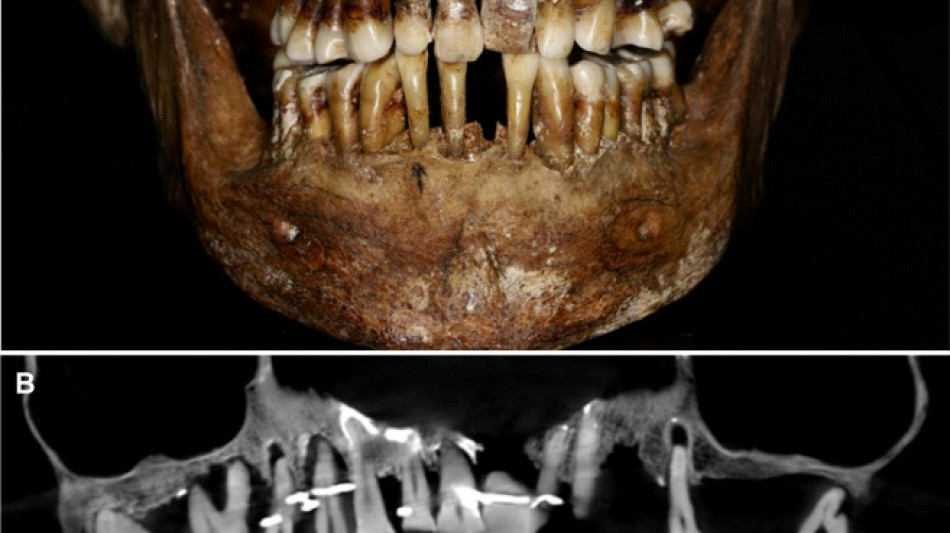

French aristocrat's golden dental secret revealed 400 years on / Photo: © INRAP/Rozenn Colleter/AFP/File

A "Cone Beam" scan, which uses X-rays to build three-dimensional images, showed that gold wire had been used to hold together and tighten several of her teeth.

She also had an artificial tooth made of ivory from an elephant -- not hippopotamus, which was popular at the time.

The gold wires would have needed repeated tightening over the years, further destabilising the neighbouring teeth, the researchers said.